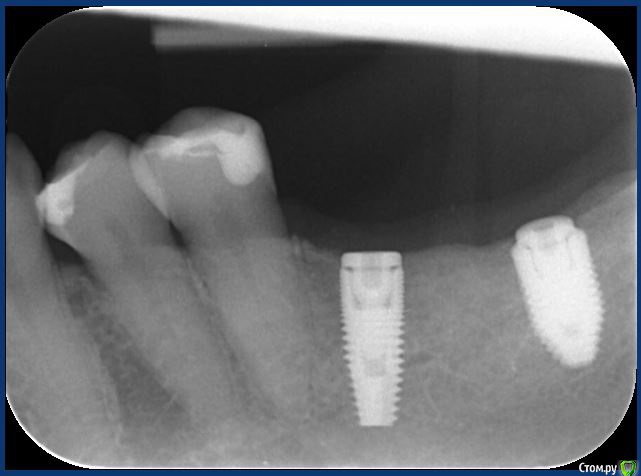

Елена67 Опубликовано 17 февраля, 2020 Поделиться Опубликовано 17 февраля, 2020 Здравствуйте, уважаемые доктора. У меня 2 месяца назад был первый этап установки 2 имплантов на нижнюю челюсть.Сейчас уже 2 недели как появились приступообразные ноющие, сверлящие боли с промежутками то болит то нет в области имплантов. Десна красная, не отечная, не кровоточит, выделений тоже нет. Если надавить на десну она не болит. В чем может быть причина болей? Помогите пожалуйста. Я переживаю что это возможно это оторжение имплантов. Прикрепила снимок и фото десны. Ссылка на комментарий

hogsmeed Опубликовано 18 февраля, 2020 Поделиться Опубликовано 18 февраля, 2020 По снимку импланты у вас стоят отлично, переживать не о чем Ссылка на комментарий

red_butler Опубликовано 18 февраля, 2020 Поделиться Опубликовано 18 февраля, 2020 заглушки не докручены, +1 к установке ФДМ Ссылка на комментарий

hogsmeed Опубликовано 18 февраля, 2020 Поделиться Опубликовано 18 февраля, 2020 заглушки не докручены, +1 к установке ФДМпросто похоже они не родные Ссылка на комментарий

red_butler Опубликовано 20 февраля, 2020 Поделиться Опубликовано 20 февраля, 2020 По снимку импланты у вас стоят отлично, переживать не о чемтолько снимок то похоже после инсталляции Ссылка на комментарий